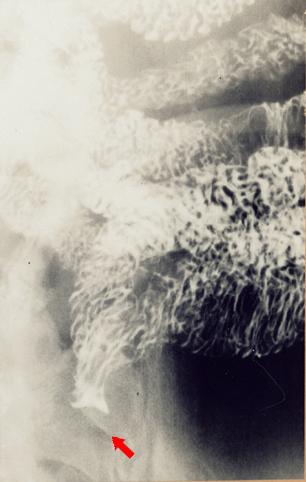

疾患(病理主体)の分類悪性非上皮性腫瘍/平滑筋肉腫(含GIST)

部位(臓器別)小腸/空腸

検査方法X-P

病変の最大径(ミリ)40以上